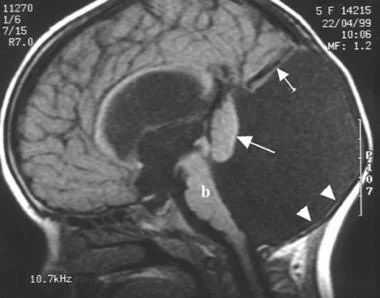

- МРТ головного мозга. Магнитно-резонансная томография в сагиттальной и аксиллярной проекции демонстрирует расширение четвертого желудочка, грубые нарушения развития мозжечка, другие структурные аномалии.

На рисунке - плод, 34 недели. Головное предлежание, гипоплазия мозжечка

На рисунке - плод, 29 недель. Агенезия мозолистого тела. Асимметричная гидроцефалия